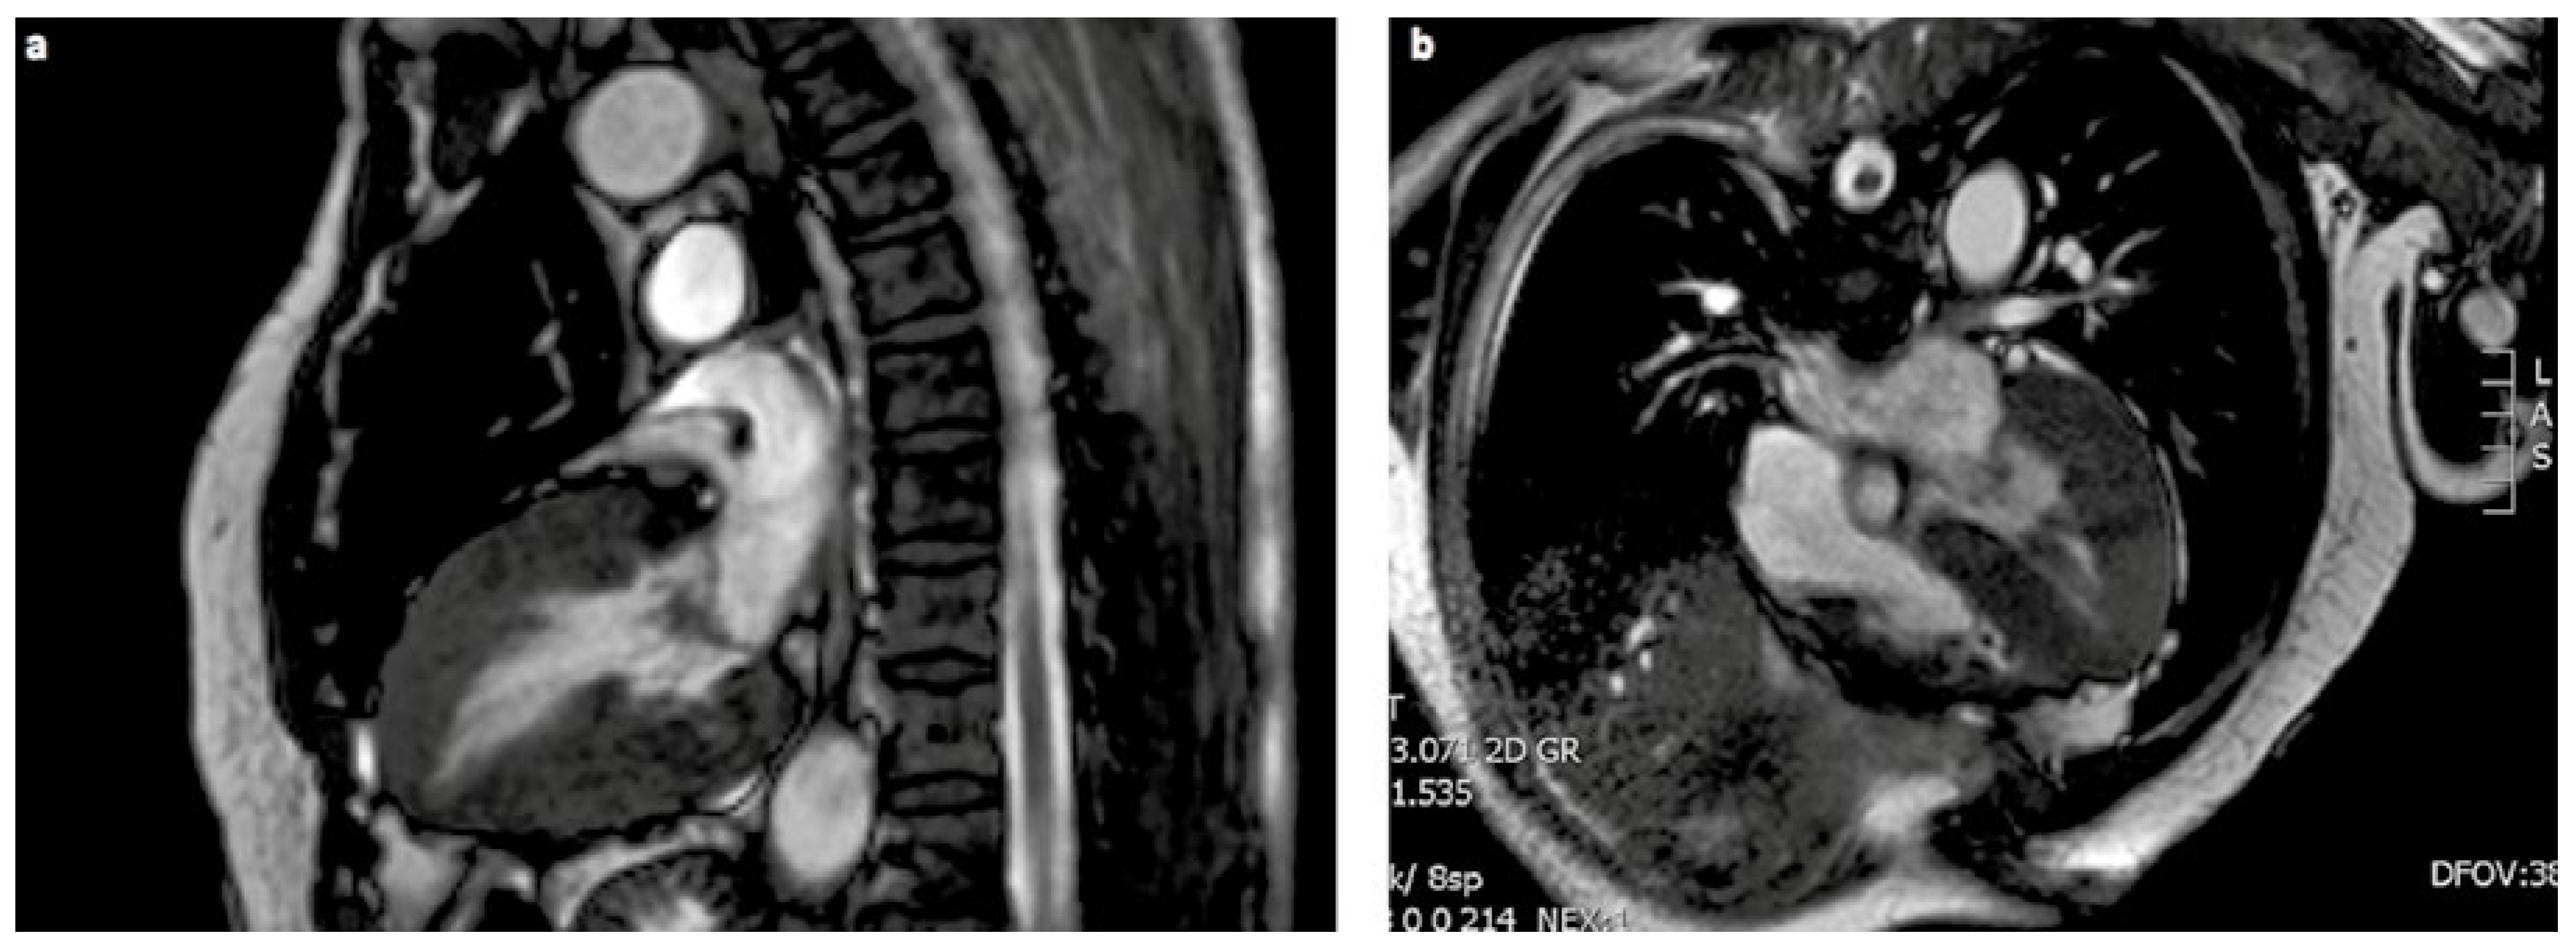

- Charakteristische EKG-Veränderungen und/oder echokardiografische veränderungen im Sinne einer linksventrikulären Hypertrophie können Manifestationen eines Morbus Fabry sein.